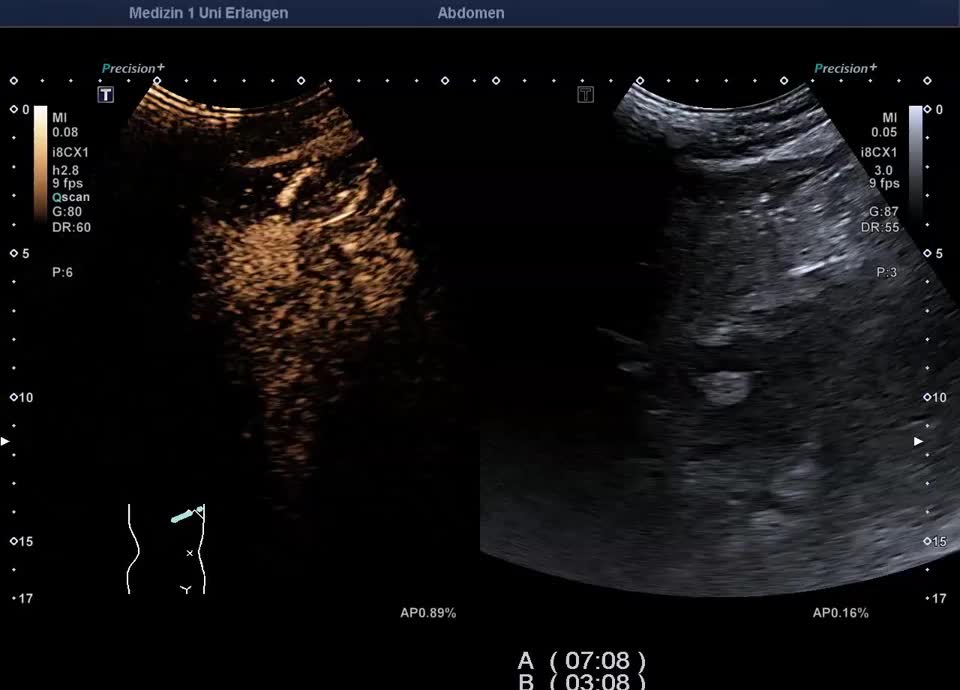

Kasuistik: 66-jähriger Patient mit seit der Jugend bekannter γ-GT-Erhöhung, sonographische Vorstellung zum Ausschluss eines cholangiozellulären Karzinoms. Sonographisch zeigt sich im B-Bild ein inhomogenes Leberparenchym mit diffus verteilten kleinen Kometenschweifartefakten im rechten Leberlappen. Das sonographische Bild ist vereinbar mit multiplen biliären Hamartomen (Von-Meyenburg Komplexe). Sie bestehen aus Zysten, die mit Gallengangsepithel ausgekleidet sind, und Bindegewebe, treten einzeln oder multipel auf und weisen typischerweise eine Größe von etwa 0,5–15 mm auf. Sonographisch stellen sie sich als echoreiche Noduli dar. Zum Ausschluss malignitätsverdächtiger Herdbefunde wurde eine kontrastmittelverstärkte Sonographie durchgeführt. Im CEUS zeigt das Leberparenchym in der portalvenösen und Spätphase homogenes Enhancement – die echoreichen Noduli sind isokontrastiert (Ausschluss Malignität). Die kleinen Zysten sind in allen Perfusionphasen nicht KM-aufnehmend. In Zusammenschau der Bildgebung und der bekannten γ-GT-Erhöhung besteht kein Anhalt für eine maligne Lebererkrankung. Eine einmalige sonographische Verlaufskontrolle wurde vereinbart.